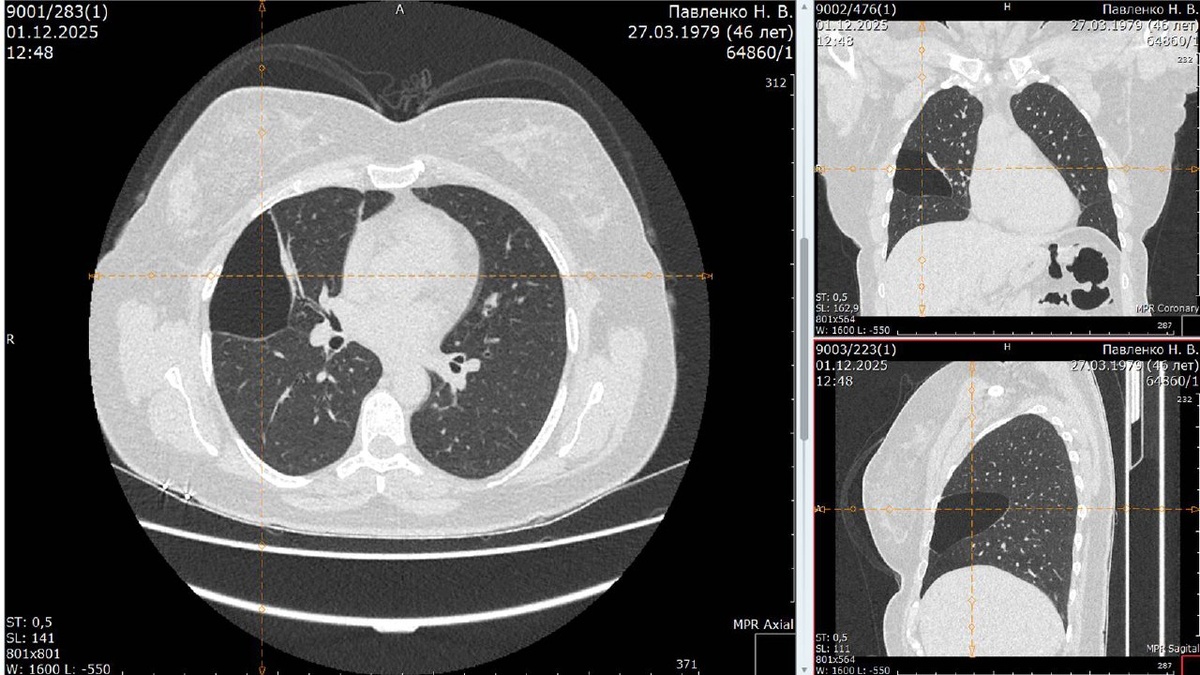

К нам обратилась пациентка П., 46 лет. На диспансеризации случайно нашли массивную буллу в средней доле правого лёгкого – полость с воздухом, которая почти полностью сдавливала долю и могла лопнуть в любой момент, вызвав спонтанный пневмоторакс (опасное для жизни состояние). Жалоб не было, но риск – высокий, поэтому выбрали хирургическое лечение.

• Провели торакоскопию (малоинвазивная операция через несколько проколов).

• Визуализировали буллу, аккуратно иссекли и удалили.

• Дефект плевры (оболочки лёгкого) ушили.

Вся операция – через проколы, без больших разрезов.